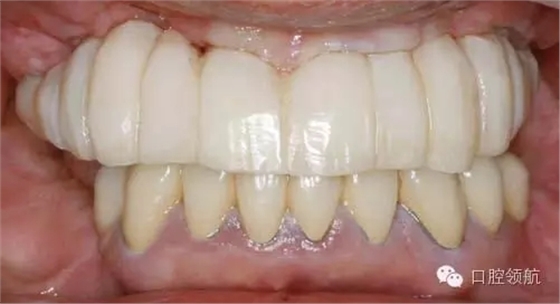

首先確認是否有炎癥表現(xiàn),結果是沒有問題(圖1)。

圖1 戴入種植體支持的上頜全口整體連接的臨時上部結構。1周后來院時訴前頭部有勒緊樣疼痛。